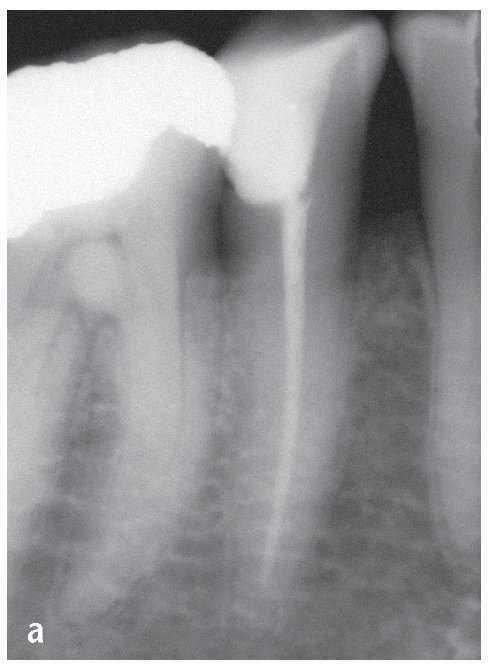

Figura 6a. Diente 47: la radiografía diagnóstica ortorradial muestra dos ápices radiculares separados en mesial y en distal. El trayecto distal del conducto parece finalizar en el tercio medio de la raíz.

Figura 6b. El sistema de conductos radiculares distal muestra una bifurcación al final del tercio medio radicular con restos de tejido en el istmo.

Figura 6c. Preparación finalizada del istmo distal.

Figura 6d. Control radiológico de las longitudes de trabajo.

Figura 6e. Vista del sistema de conductos distal con filtro UV antepuesto, dado que se utiliza un sistema de sellado adhesivo: obturación de los segmentos del conducto en apical de la furcación.

Figura 6f. Situación clínica después de la obturación termoplástica.

Figura 6g. La radiografía de control después de la obturación con técnica de inyección muestra el sistema de conductos radiculares completamente obturado junto con los istmos y algunos conductos laterales así como pequeñas extrusiones de material.